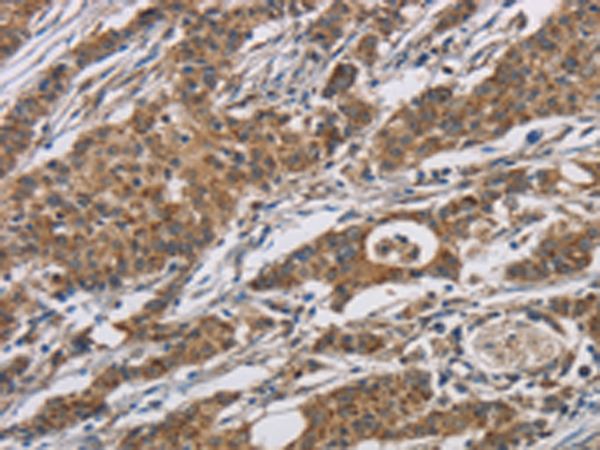

分类: 科研抗体货号: P06944别名: FN; CIG; FNZ; MSF; ED-B; FINC; GFND; LETS; GFND2应用: IHC反应种属: Human, Mouse, Rat